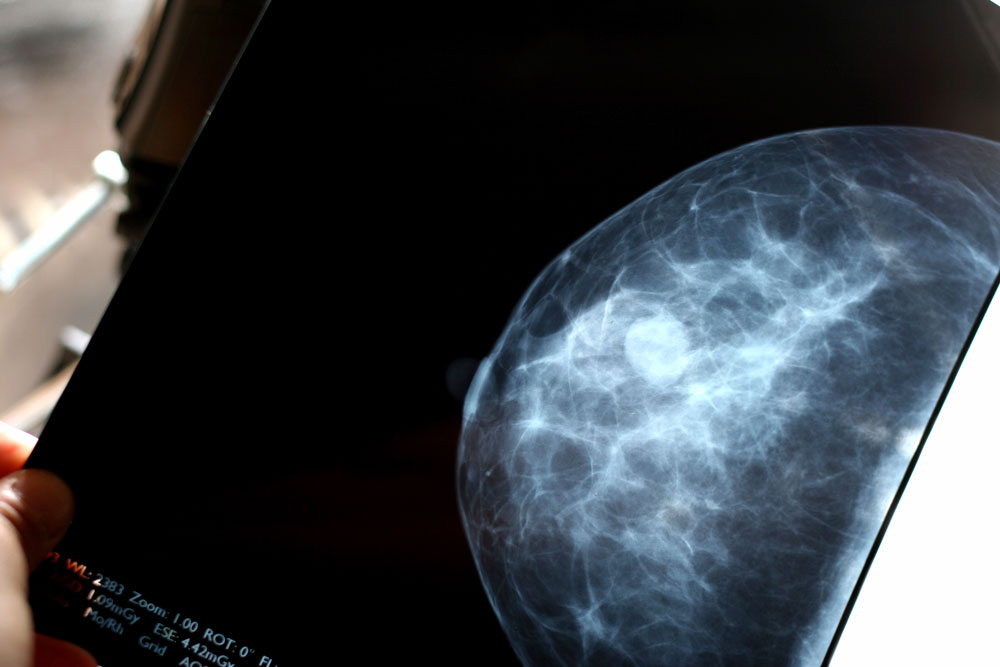

A molecular test can pinpoint which patients will have a very low risk of death from breast cancer even 20 years after diagnosis and tumor removal, according to a new clinical study led by UC San Francisco in collaboration with colleagues in Sweden. As a result, “ultralow” risk patients could be treated less aggressively and overtreatment avoided, leading to fewer toxic effects.

In the new study, researchers sought to determine whether a 70-gene test could accurately and reliably identify tumors with indolent, or slow-growing, behavior to assess the risk of cancer recurrence up to 20 years after diagnosis. The same test had shown last year that nearly half of early-stage breast cancer patients, who met traditional criteria for high risk, could safely skip chemotherapy based on the biological makeup of their tumors.

The authors disclosed that the test, called MammaPrint®, was devised by UCSF cancer researcher Laura van ‘t Veer, PhD, a co-author on the new study and co-leader of the breast oncology program at the HDFCCC. Produced by Agendia, a company co-founded by van ‘t Veer, MammaPrint® tests for a 70-gene signature that can predict whether cancer will recur in early-stage breast cancer patients. It was approved by the U.S. Food and Drug Administration in 2007.